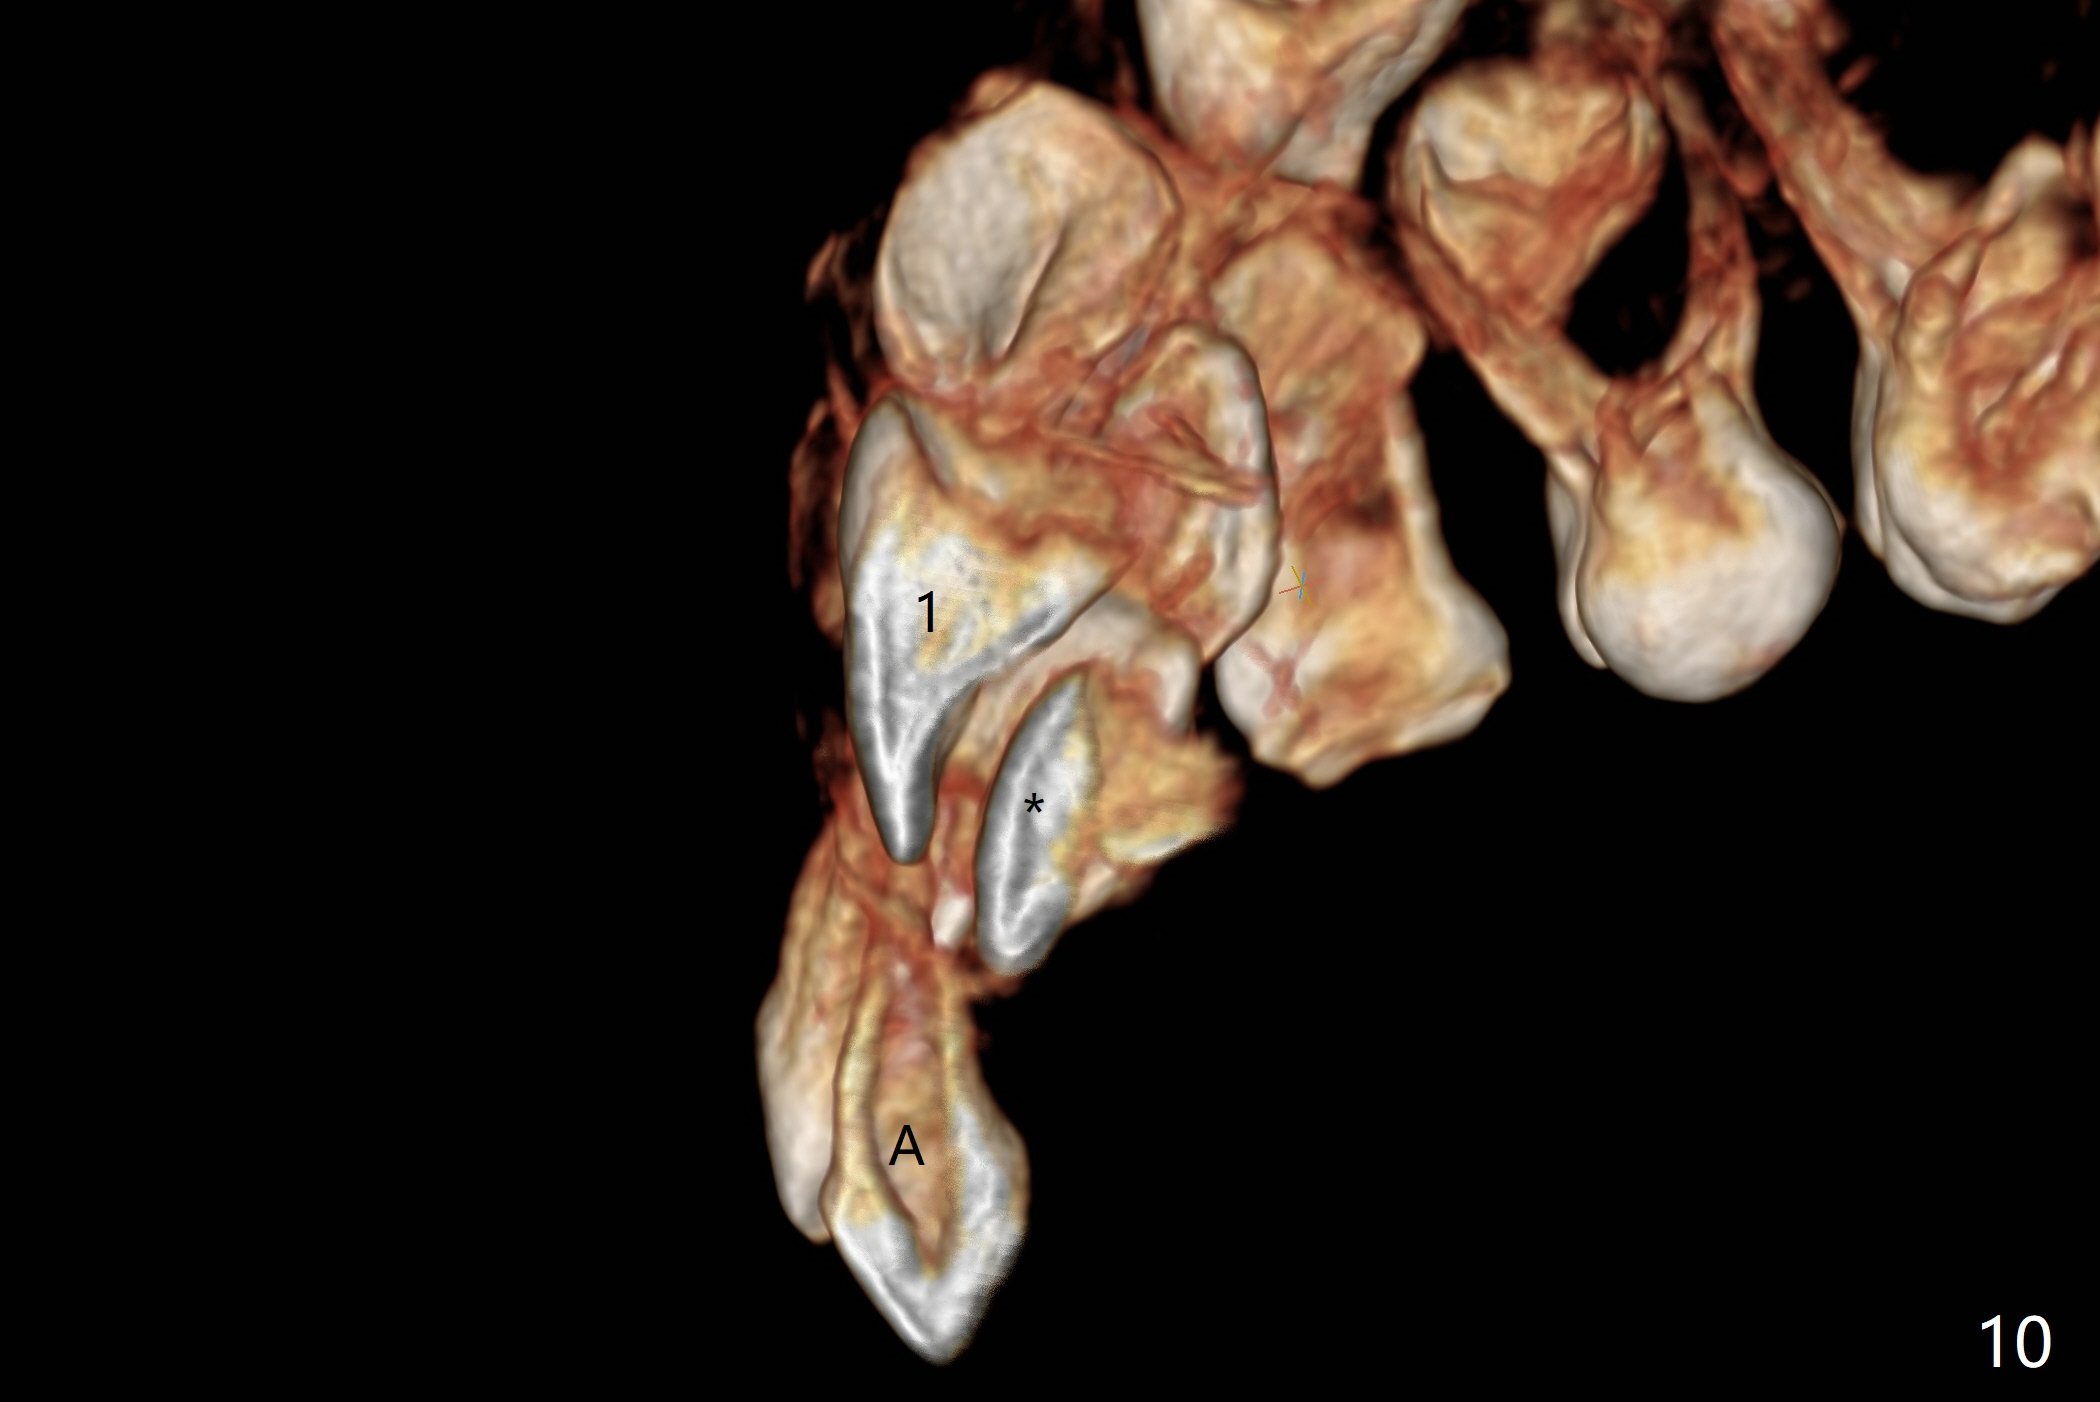

Reanalysis of 3 D images (Fig.7 (frontal view), 8 (posterior view), 9 (lateral view), 10 (lateral view with section) of CT taken 1 year 3 months earlier shows that the mesiodens (*) and the permanent lateral incisors (2) are palatal to the permanent central incisors (1) and canines (3) and the deciduous central incisors (A).  The supernumerary teeth do block the eruption of the permanent central incisors (Fig.10).